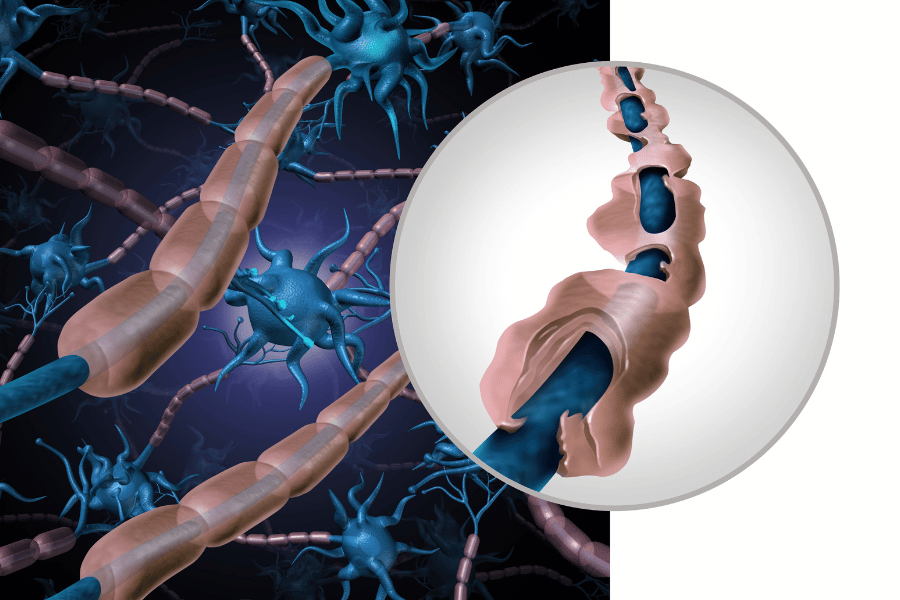

הלבלב, כמו הכבד, הינו בלוטה, ובניגוד לכבד הוא קטן יחסית – משקלו הוא כ-100 גרם ואף פחות ואורכו 15 ס"מ. למרות זאת מדובר באיבר רב חשיבות הלוקח חלק נכבד בתהליך העיכול ומייצר מיצים המכילים אנזימים שבלעדיהם לא ניתן לפרק את כל אבות המזון.

המעי הדק הוא אחת התחנות שבהן עובר מזון במסגרת תהליך עיכולו – התחנה בה מתבצע עיקר ספיגת החומרים החיוניים לגופנו.

אורכו של המעי הדק, אשר מונח בתוך חלל הבטן שלנו בצורה מפותלת, נע בין 6 ל-8 מ' וקוטרו הוא כ-3 ס"מ. האנזימים המגיעים אליו מן הלבלב מפרקים פחמימות לחד סוכרים, חלבונים לחומצות אמינו ושומנים לחומצות שומניות וגליצרול. בדיקת ה-MRE מתבצעת בעיקר על מנת לאבחן היווצרות מחלות כרוניות של המעי הדק (קוליטיס וקרוהן).